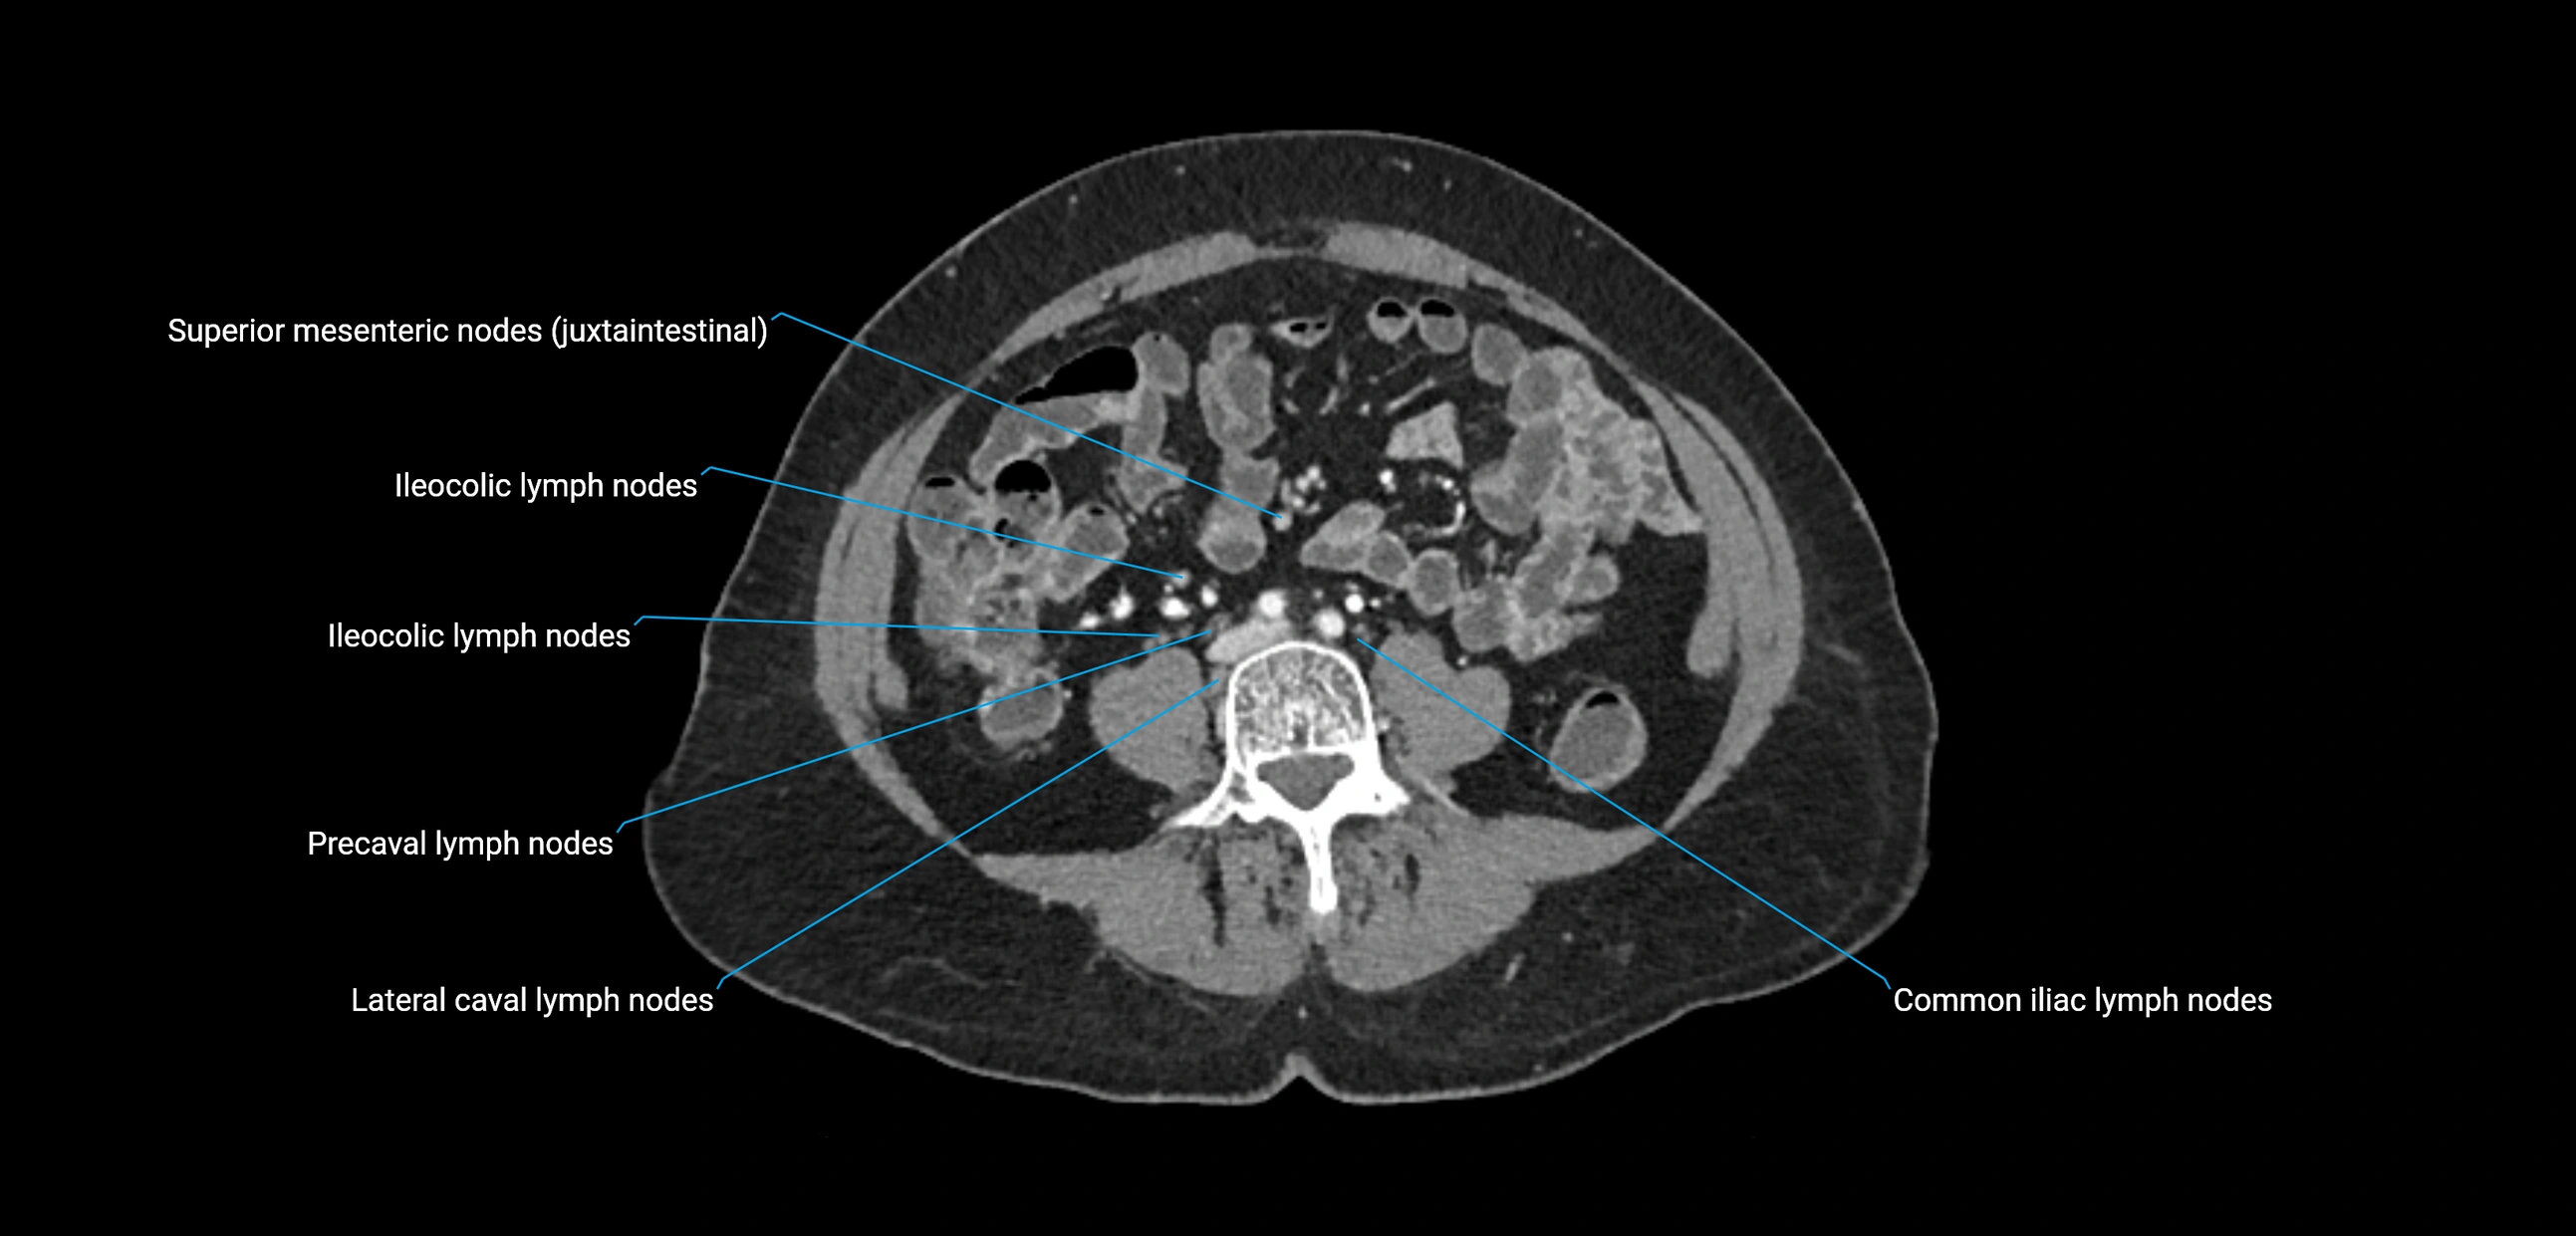

CT Appearance

CT Pre-Contrast:

• Nodes appear as soft-tissue density nodules adjacent to the aorta and IVC

• Calcification may be seen in chronic infections (e.g., tuberculosis)

CT Post-Contrast:

• Normal nodes enhance homogeneously

• Malignant nodes may show heterogeneous enhancement, central necrosis, or conglomerate formation

• Size >1 cm short axis is suspicious, though morphology and distribution are equally important